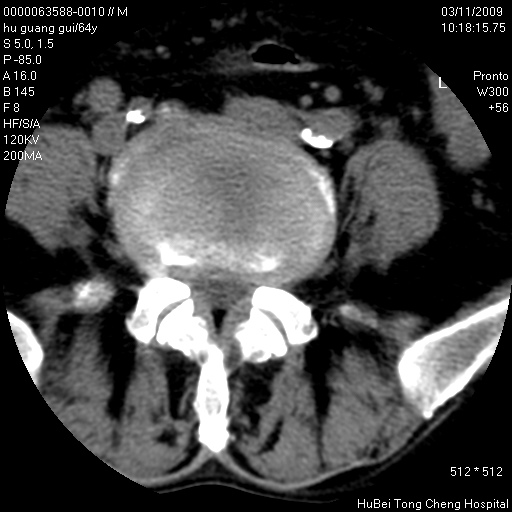

患者 男,64岁。腰痛十余天。(临床未提供其他病史)

临床诊断:腰痛原因待查(腰椎间盘突出症?)。

腰椎间盘ct轴位平扫(层厚5mm,层距4mm),图像如下:

腰椎退行性变,腰4—5椎间盘膨出。

1.腰椎退行性变,腰4—5椎间盘膨出。

1)腰椎退行性变,l4—5椎间盘膨出。2)骶骨右侧块骨转移瘤可能,3)水平骶椎。建议作一步检查。